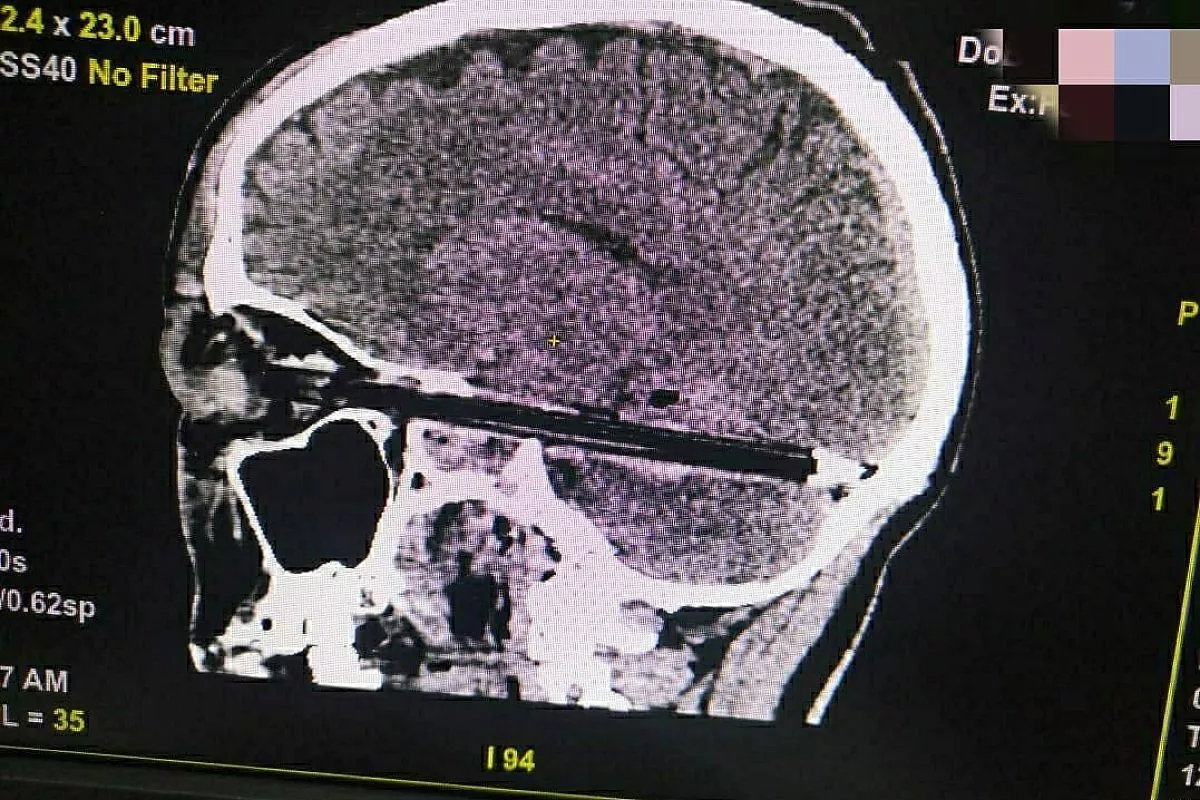

Мужчина 37 лет был экстренно доставлен в медучреждение с проникающим колотым ранением глазной орбиты и головного мозга. В глаз пациенту вонзилась шариковая ручка. Повредив глазное яблоко, она вошла в мозг на весь диаметр полости черепа – от передней до задней черепных ямок.

– Ювелирная операция по извлечению инородного предмета из глаза и головного мозга пациента проводилась с помощью новейшего медицинского оборудования. Шариковая ручка прошла в миллиметре от важнейших сосудов и ствола головного мозга, чудом не повредив их. Чтобы провести ее тракцию максимально осторожно, потребовалось мастерство врачей. И это было сделано на высочайшем уровне, – говорится в Instagram-аккаунте больницы.

После операции пациенту провели контрольное обследование на КТ и переместили его в реанимацию.